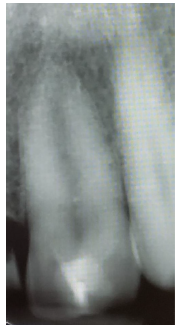

Radiograph and intraoral examinations reveal worn-down teeth [#s 07, 08 and 09] (Figures 1-5) as well as tooth gemination [# 10] (Figures 1-7). The evaluation of periapical radiographs taken of teeth [#s 07, 08, 09, and 10] presents with no evidence of periapical radiolucency. Tooth [# 08], however, shows significant internal root resorption to the mid-way and calcified the apical half of the root to the apex. Tooth [# 09] also shows a significant external/internal root resorption which is more evident on the distal aspect of the tooth, (Figure 7). Both merged segments of geminated tooth [#10] (Figure 6), shows almost completely calcified root canals to the apex. This calcification is also evident in tooth [# 07] (Figure 7).

Figure 6: Germinated/Double tooth with completely calcified root canals.

Figure 7:Teeth #s 08 & 09 radiographic evidence of external / internal root resorptions & partially calcified root canal.